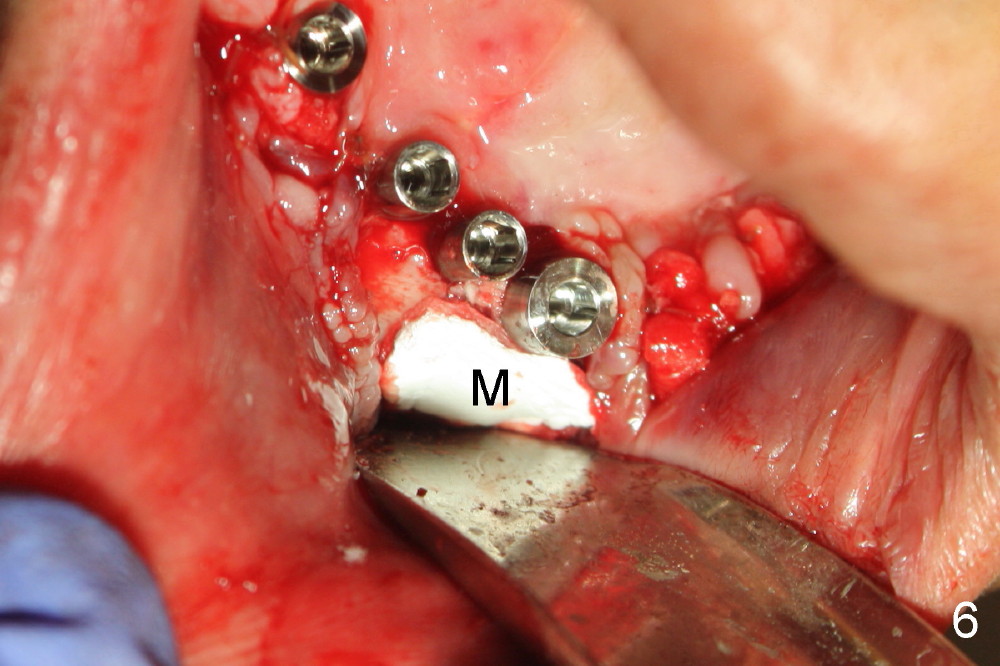

Osteotomy is initiated through the gingiva of the healing sockets at the sites of #22 and 27 (Fig.1) with difficulty (close surgery). The incisor crest incision is extended distal to the canine areas; an accessory oblique incision is supplemented to facilitate implantation (#22: 5x14 mm; #27: 4.5x17 mm) and expose the buccal defects (Fig.3,4, open surgery). The defects are grafted (Fig.5) and covered by collagen membrane (Fig.6). The incisions are closed and abutments are placed for immediate provisional (Fig.7).